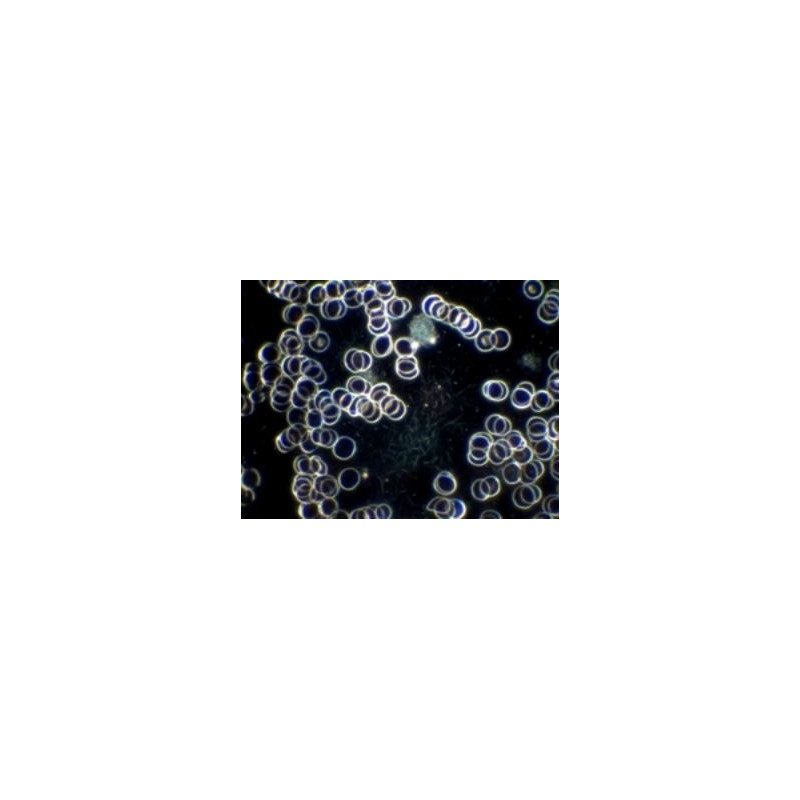

Optimales Dunkelfeld-Bild mit Objektiv SPL 100/1,25 Oel mit Irisblende

Das H 600 LL HP 100 wurde speziell für die Untersuchung von Nativblut nach der Methode von Prof. Enderlein entwickelt. Durch diese Methode können Blutzellen und Plasma qualitativ bestimmt werden. Es gewährleistet die Analyse von Form und Funktionsfähigkeit der Blutzellen sowie deren Befall durch Mikroorganismen.

Eine einfache und fehlerfreie Diagnose wird durch eine hohe Vergrößerung, höchsten Kontrast und die höchste Auflösung erreicht.